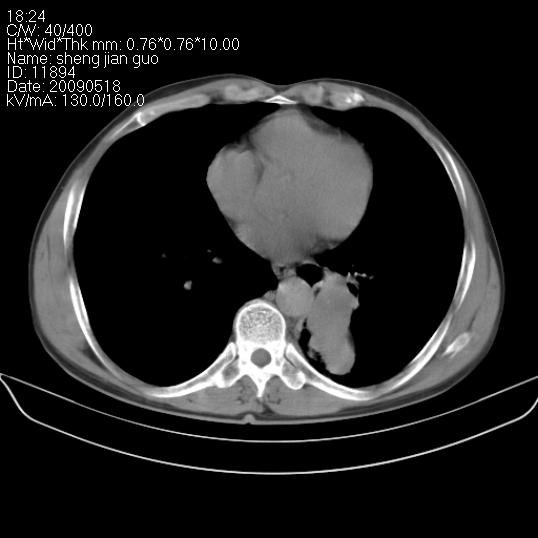

以下是引用zjzjr在2009-5-19 17:25:00的发言:[br]支持楼主考虑,另左肺下叶阻塞性炎症。

以下是引用zhao_bin2008在2009-5-19 17:48:00的发言:[br]支持左肺下叶周围型肺癌并阻塞性肺炎。

以下是引用zsl6918在2009-5-20 7:10:00的发言:[br]左侧中心型肺癌!